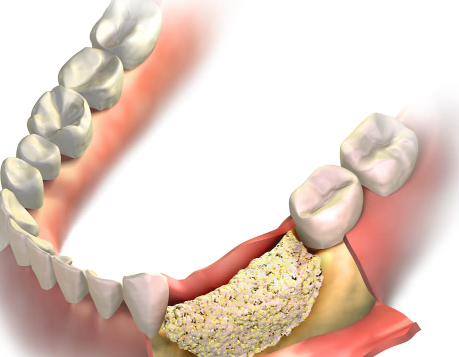

치아가 빠진 자리의 잇몸뼈는 마치 사용하지 않는 근육이 줄어드는 것처럼, 시간이 지날수록 급격히 감소합니다.

특히 발치 후 1년 동안 가장 빠르게 뼈가 줄어들어, 이후 임플란트 시술이 훨씬 더 복잡해질 수 있습니다.

잇몸뼈가 부족해지면 임플란트 식립을 위해 뼈 이식이 추가로 필요할 수 있습니다.

이는 마치 무너진 땅에 집을 짓기 전에 지반을 다시 다지는 것과 같습니다.